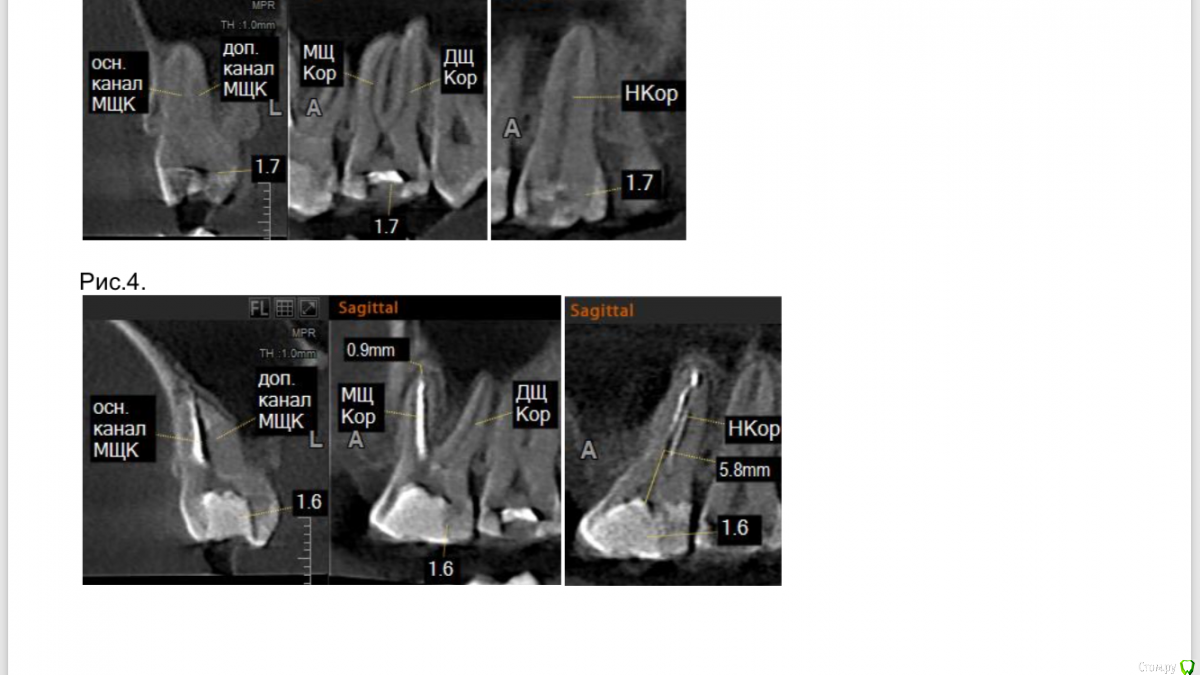

Пушканчик Опубликовано 1 апреля, 2019 Автор Поделиться Опубликовано 1 апреля, 2019 6-й зуб на рис.4 Ссылка на комментарий

Пушканчик Опубликовано 1 апреля, 2019 Автор Поделиться Опубликовано 1 апреля, 2019 Со стороны лунки 5-го жалоб нет, но она так и не заросла, покрылась эпителием и ушла вглубину. 7-й зуб перепломбирован 23.03, кариес дошёл до пульпы, сделали подкладку на пульпу и зуб закрыли световой пломбой, вроде не болит, но если честно нормально оценить, что конкретно болит, я уже не в состоянии. На данный момент точно болит 6-й зуб, челюсть вокруг него, область неба вокруг него, отдаёт в щеку, под глаз, в область носа и уха, щеку как бы печёт, и под глазом отек. Ссылка на комментарий